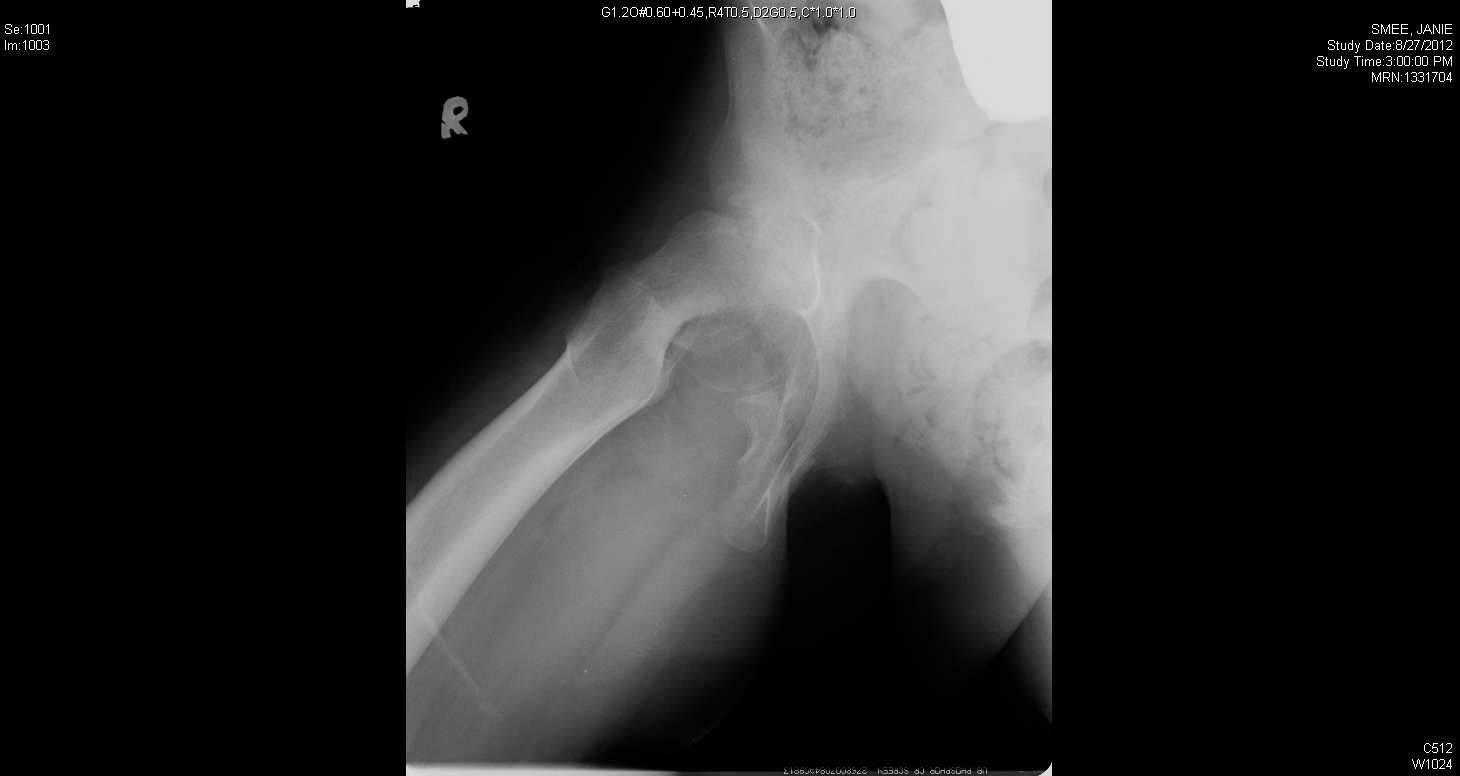

Femoral head fused to the back of the neck from a severe slip

Femoral head fused to the back of the neck from a severe slip.